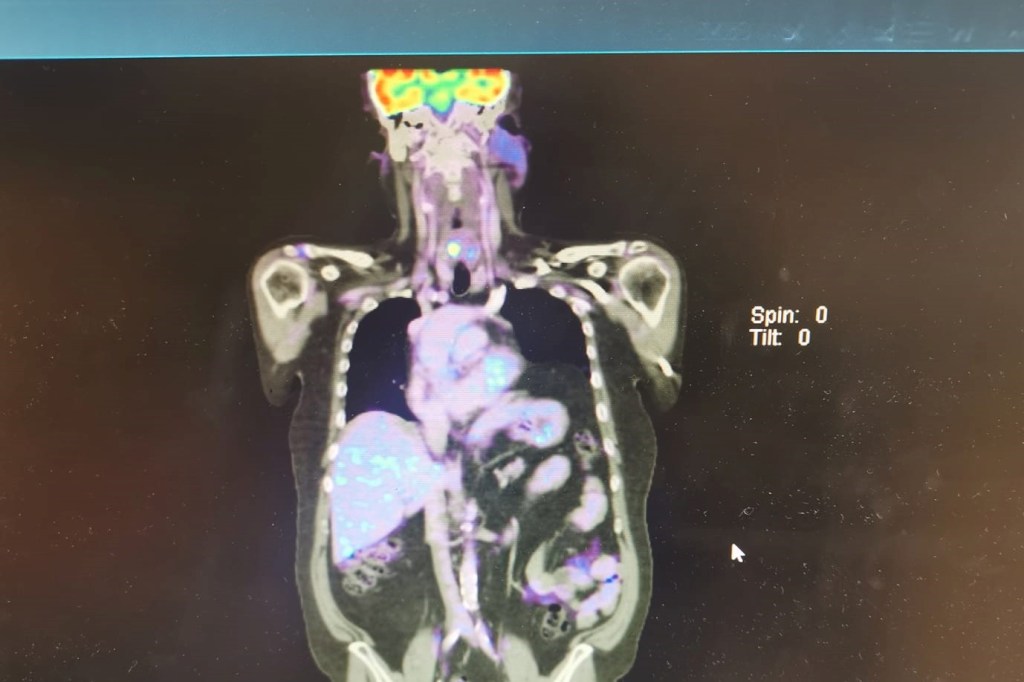

Things continue to improve in almost all areas. While I am not in remission yet it’s closer with every scan. Just the area of my first left rib is proving to be a stayer but my haematologist had said that this would be the slowest area to respond to treatment as it’s in the bone rather than a lymph node. One surprising result was to see the activity in my Arytenoid (vocal cords) this can be clearly seen in the above photo, the white/blue spot in the middle of my neck. The pet scan report puts this down to being most likely an inflammatory condition. I hope that’s the case as I have been coughing more than normal over the last couple of weeks. I guess the next scan which is scheduled for eight weeks from now will reveal more.